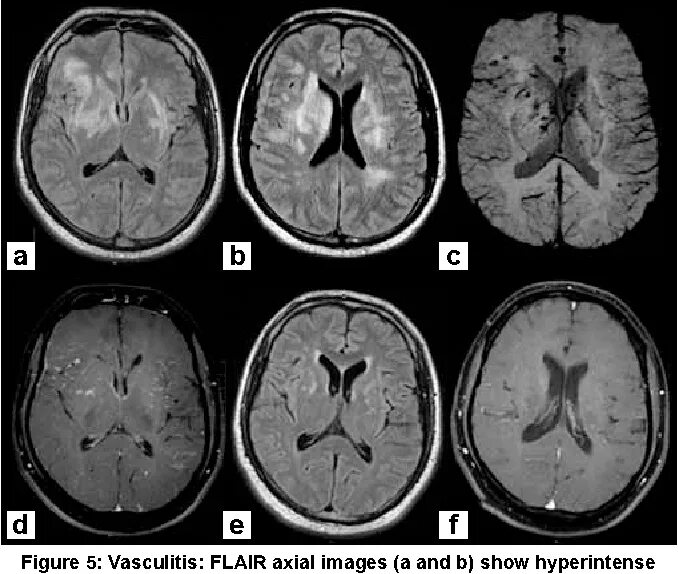

Субкортикальные очаги в лобных долях